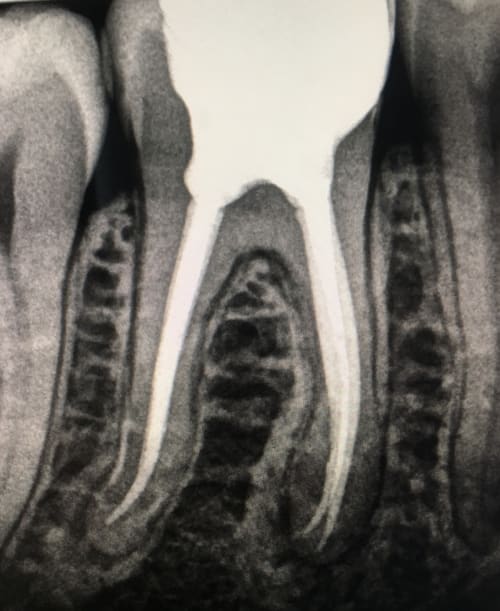

• Auf dem Röntgenbild sind an der Wurzelspitze dunkle Felder zu erkennen

• Das Röntgenbild zeigt, dass die Wurzelfüllung über die Wurzelspitze hinaus geht

Feinste Strukturen wie Nebenkanäle oder Verzweigungen können besser aufbereitet werden als bei der klassischen Wurzelspitzenresektion. Dadurch wird eine erneute Infektion des inneren Zahnes vermieden. Da nur erkranktes Gewebe entfernt und der Zugang zur Wurzelspitze klein gehalten wird, werden Schmerzen, Wundheilung und Narbenbildung verbessert. Das umliegende, gesunde Gewebe wird somit optimal geschont. Die ausgefeiltere Technik ermöglicht zudem eine bessere Beurteilung des Behandlungserfolgs im Röntgenbild.

Dies lässt sich röntgenologisch genau feststellen und definieren.

Die Regeneration des Knochens an der behandelten Wurzelspitze ist ein Beweis für die vollständige Wiederherstellung der vollen Kaufunktion.